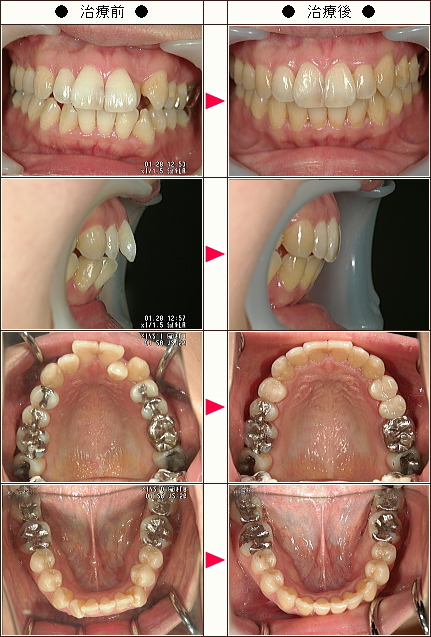

歯のデコボコ矯正症例[S.I.様 34歳 女性]

| 主訴 | 上下の前歯のでこぼこ |

| 治療方法 | ワイヤー7か月 マウスピース6か月 |

| 治療期間 | 13カ月 |

| 費用(税込み) | 121万円 |

| 治療等の主なリスク、副作用 | 奥歯を親知らずの方向に動かすために親知らずの抜歯は必須になります 下顎の前歯のブラックトライアングルの改善のために、下の前歯の隣接面を削りました |

| 治療詳細 | ワイヤー矯正で奥歯を外側に広げて、親知らずの方向に移動して、できたスペースを利用してマウスピースで前歯を中に入れました |